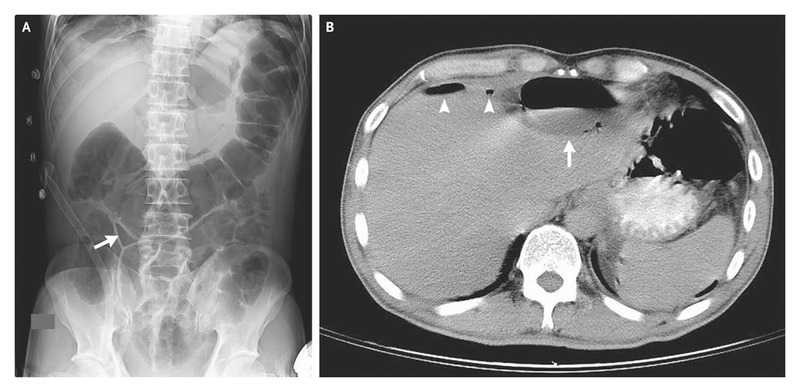

Supine plain radiography of the abdomen revealed a small triangular pocket of air outlined by three adjacent bowel loops (Panel A, arrow), a finding that was consistent with the presence of free intraperitoneal air; this is known as the telltale triangle sign.

Abdominal computed tomography confirmed the presence of pneumoperitoneum (Panel B, arrowheads) and also showed a subdiaphragmatic abscess with an air–fluid level (Panel B, arrow).